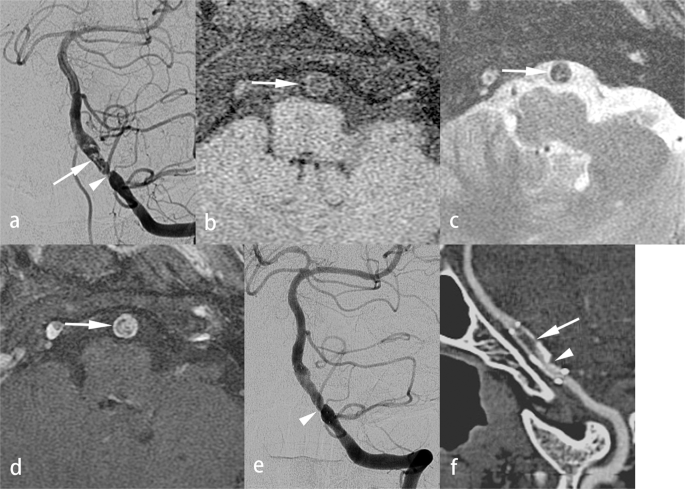

PTAS was performed successfully in 30 of 31 patients (96.8%), under local anesthesia in 20 patients, and under general anesthesia in 11 patients. One patient failed stenting because the patient’s hard stenotic lesion could not be adequately dilated by an inflation pressure of 7 atm (Fig. 2). The Wingspan stent system failed to pass through the target lesion, leaving significant residual stenosis. The patient’s condition was complicated by slight dissection of the basilar artery and a perforator stroke due to pontine infarction. For all patients, the mean PP was 4.7 ± 1.8 (2–7) atm. Technical complications were noted in 11 patients (35.4%). They included perforator stroke in the brainstem of 7 (22.5%) patients and transient ischemic attack in 4 (12.9%) patients. In the 30 patients successfully treated with PTAS, recurrent neurological ischemia was noted in 3 of the 5 patients with severe ISR: 2 of the 3 patients died of a major stroke and one experienced a TIA.

Hard lesion in a patient with atherosclerosis. A 73-year-old man suffered from recurrent stroke in the bilateral occipital regions. Left vertebral angiogram showed atherosclerosis with 90% stenosis of the mid-basilar artery (a, arrow). VW-MRI of the stenotic lesion of the mid-basilar artery revealed low signal on fat-suppressed T1WI (b, arrow) and T2WI (c, arrow) and strong enhancement on contrast-enhanced fat-suppressed T1WI (d, arrow). The PTAS failed because the stenotic lesion could not be fully dilated with the PP up to 7 atm (e, arrow). The Wingspan stent system could not pass through the stenotic lesion. His case was also complicated by a perforator infarct in the left pons (f, arrow).